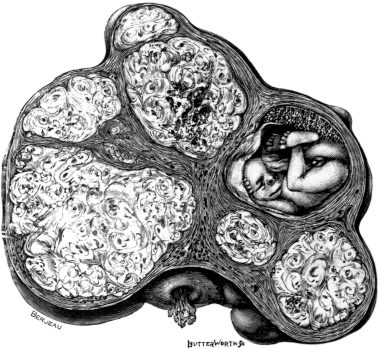

| 8. | A Gravid Fallopian Tube, containing Twins | 32 |

| 9. | A Diagram to show the Arterial Supply of the Uterus | 37 |